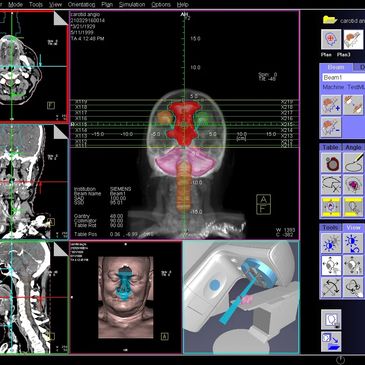

Clinical Scientists play a central role in developing, planning and implementing patient treatment programmes. They work closely with other healthcare professionals in research, development, testing, and maintenance of specialist medical equipment.

Clinical Scientists work closely with other healthcare professionals in research, development, testing, and maintenance of specialist medical equipment. They play a central role in developing, planning, and implementing radiotherapy patient treatment programmes. You might be interested in the career if you are interested in science (particularly physics) and healthcare.

As a Clinical Scientist you will be involved in:

Clinical Technologists (also known as Healthcare Science Practitioners) are responsible for planning an individual patient’s treatment, using complex computer algorithms.

As a Clinical Technologist you will be involved in: